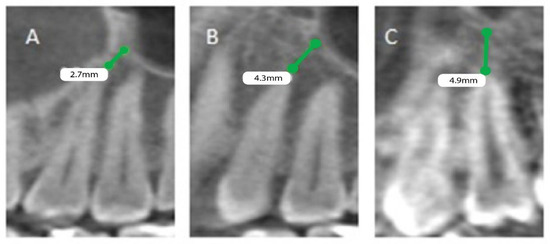

The patients’ files were assessed by the Department of Oral & Maxillofacial Surgery and Diagnostic Sciences, College of Dentistry, Prince Sattam Bin Abdulaziz University, Al-Kharj, Saudi Arabia, to record the gender and the age of the subjects included in the study from September 2020 to December 2020, and further divided as male and female patients, depending on gender and age, into 4 groups (0 to 20, 21 to 40, 41 to 60, and above 60). Mean distances between posterior maxillary roots (PMRs) from different teeth and the maxillary sinus floor (MSF) were measured using a software-calibrated tool. Each measurement was obtained by measuring a line drawn from the MSF to the nearest point of the apex of the root in two views, sagittal and coronal, and the mean distance was calculated (Figure 1, Figure 2 and Figure 3). The distance for each root and each tooth were recorded and transferred to the Excel sheet.

Figure 3.

CBCT sagittal view showing the distance between the maxillary sinus and the root of permanent maxillary. (A) Right first and second molars with mesiobuccal and distobuccal roots, (B) left first molar mesiobuccal root, and (C) left second molar palatal root.